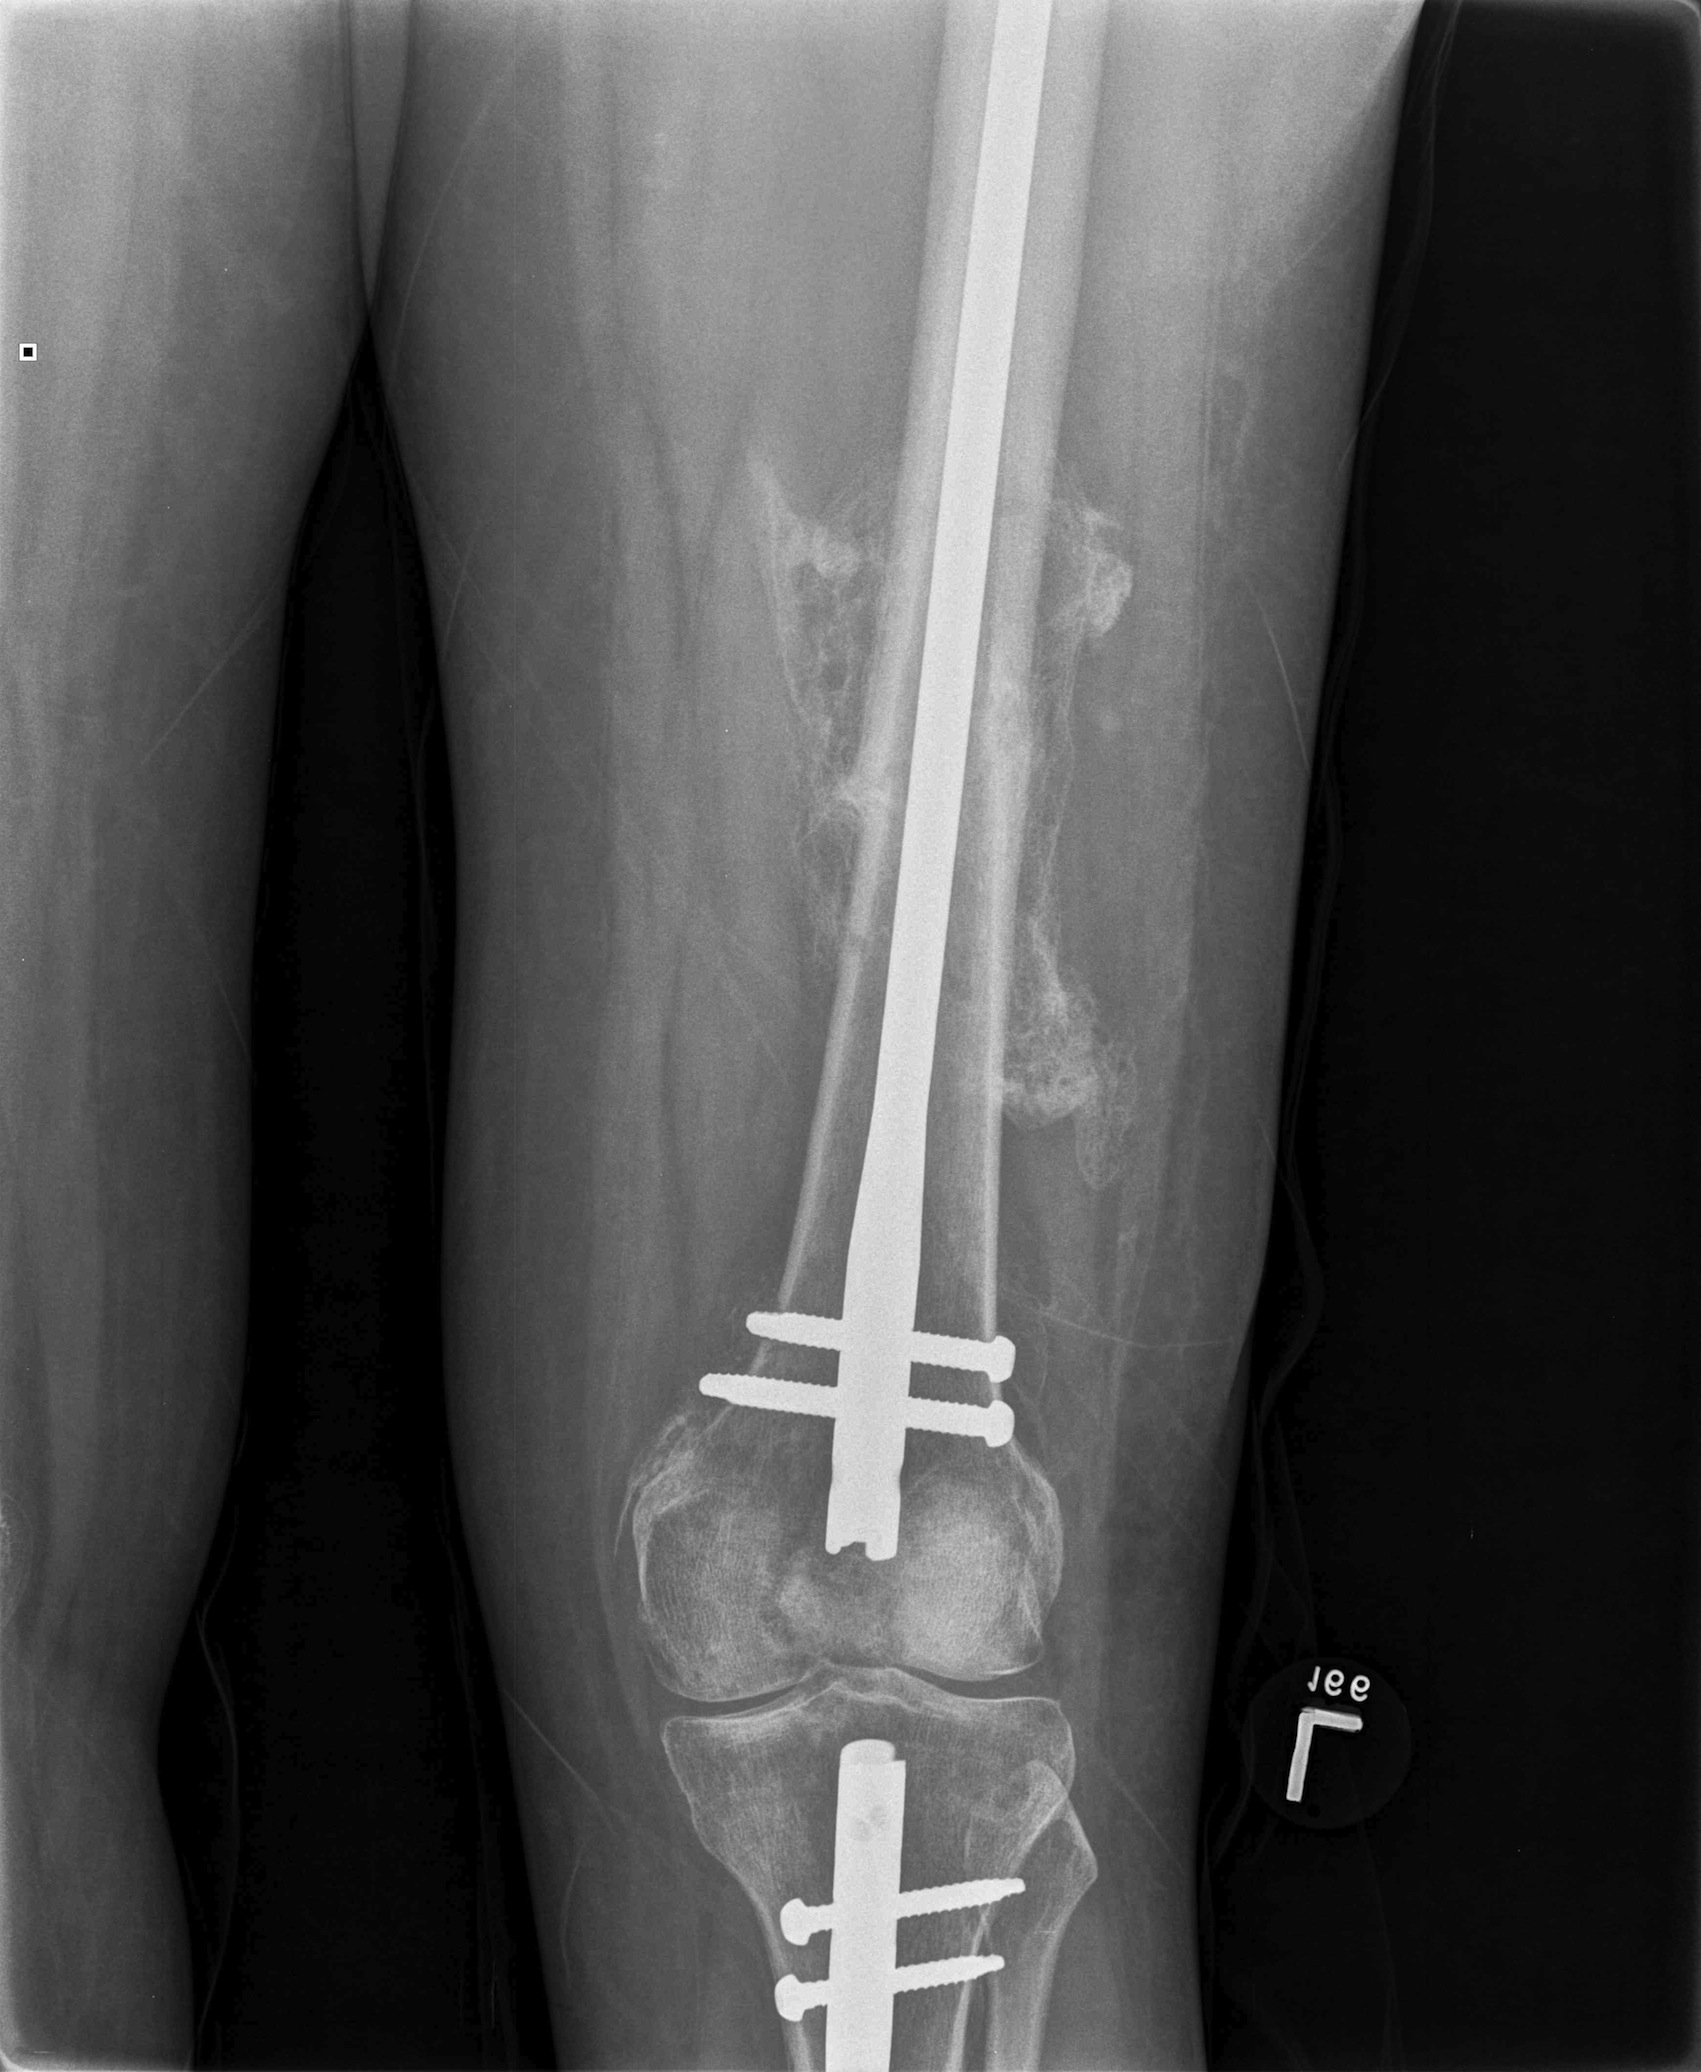

2. NOF (Neck of Femur) + Femoral shaft fracture

Must pay attention first to meticulous NOF ORIF

Options

1. Pin and Plate NOF / Retrograde Nail

2. Pin and Plate NOF / Plate femur

3. Reconstruction Nail

- difficult to anatomically reduce NOF

- increased incidence NOF non union

Results

Ostrum et al. CORR 2014

- 95 cases treated with proximal screws / sliding hip screws inserted first

- retrograde IMN second

- 98% union rate femoral neck

- 91% union rate femoral shaft